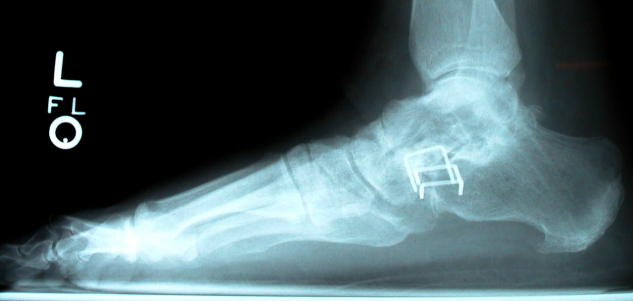

Since the posterior tibialis forms the arch of the foot, it was necessary to replace its function with a permanent arch formed by various bones of the foot. July 28, 1999 Dr. Cooper operated, using titanium screws and staples to hold three joints – the subtalar, calcaneocuboid, and talonavicular – in position until the bones became permanently fused. To make sure the bones fused properly, he also removed some bone from the tibia, just below the knee – necessitating another incision – ground it, and packed it between the four bones involved: the talus, calcaneus, cuboid, and navicular.

Six weeks later the cast was removed (stitches were removed after two weeks, through "windows" that were left in the cast) so the foot could be X-rayed in a natural position to determine that healing was progressing as desired.

The removal, in March 2000, was an outpatient procedure and after a week she got the stitches removed. The screw holes, which can still be faintly seen, would fill in within a few weeks. The staples, however, remain, of interest to airport metal detectors.

It took a while for her to get walking in shoes again, and back to the gym. It has taken another year to get back to "normal," although she no longer has lateral flexibility in the foot.